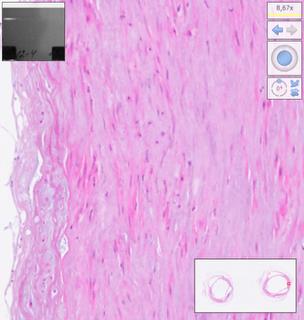

Histological examination was performed on days 7, 14, 21, 28, 35, 42, 49, 56, 63, 70, 77, 84 after homograft collection, ten arterial and ten venous preparations respectively. Twelve comparison groups of arterial and venous homografts were obtained. One hundred twenty arterial and 120 venous specimens were studied. The number of myocyte nuclei in the middle layer of homografts was estimated using automatic counting in the Image-PRO Plus 6.0 program (Figure 1) and recalculation of the obtained values per 0.01 mm2 (10,000 μm2) of the area of the middle layer of the vessel homograft wall. Counting was performed in 1 field of view at medium magnification (×100) using digital processing to visualize muscle cell nuclei. The software used was NDP.view2 (U12388-01; Hamamatsu Photonics KK).

Fig. 1. The stages of digital processing of the homograph wall (magnified ×100).